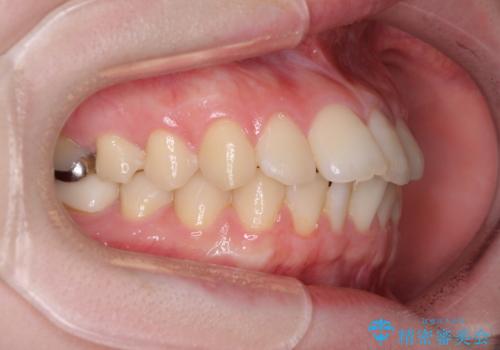

デコボコ歯列をきれいに インビザラインによる矯正治療

- 上下歯列全体のデコボコを気にして来院された患者様です。

主に下顎歯列全体の後方移動とIPR(歯と歯の間を削る)によってデコボコが解消するように設計し、インビザラインにより治療を行うこととしました。

1年半程度で終了するのではないかと予想しましたが、途中1年以上の来院がなく、トータルで3年の時間がかかってしまいました。

前歯のデコボコはより改善することが望ましい状態でしたが、患者様の希望により終了することとなりました。